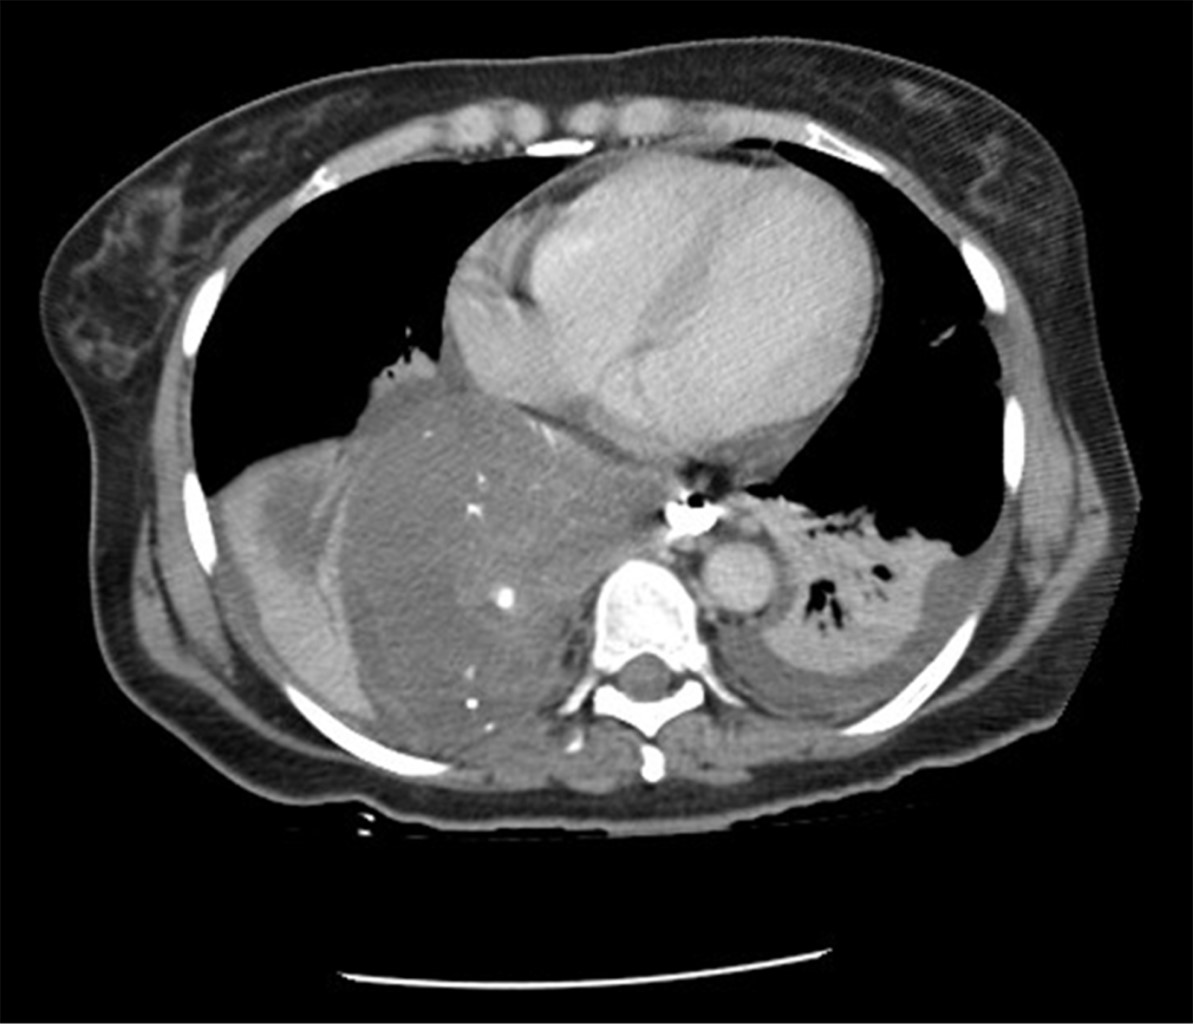

This is the case of a 54-year-old woman with a history of systemic arterial hypertension of 16 years of evolution in medical treatment with losartan 50 mg every 24 hours in reasonable control, history of total abdominal hysterectomy 14 years ago for uterine myomatosis, laparoscopic cholecystectomy four years ago for chronic calculous cholecystitis, both without apparent complications. She started with 36 hours of evolution with significant chest pain, unquantified fever, and attack to her general condition, so she came to our unit for evaluation. When specifically interrogated, she mentioned a history of five years of symptoms characterized by dysphagia to the ingestion of solid food. Physical examination revealed a patient in poor condition with tachycardia of 120 beats per minute, hypotension of 90/60 mmHg, respiratory rate of 23 breaths per minute, temperature of 36.5 °C, and generalized pallor of the integuments. The auscultation of the chest on the right side revealed decreased breath sounds with dullness to percussion. Her abdomen was flat, soft, and depressible with increased vocal vibrations, with no evidence of peritoneal irritation. Laboratory tests showed hemoglobin 16.6 g/dl, hematocrit 49.68%, white blood cells 18 cells/mm3, and neutrophils 89%. A thoracoabdominal tomography was performed, which showed a distal esophagus-dependent tumor associated with free fluid in the thorax and exit of contrast medium from the esophageal lumen (Figures 1 and 2). Due to the clinical picture of esophageal perforation and mediastinitis, it was decided to submit the patient to surgical treatment.

Imaging studies such as barium esophagogram, computerized tomography scan with oral contrast, esophagoscopy, and endoscopic ultrasound are helpful diagnostic tools in this pathology.17 In the present case, the thoracoabdominal tomography revealed a large tumor originating in the lower third of the esophagus, which after administering an oral contrast medium, showed a perforation of this organ, requiring emergency surgery.

Figure 2